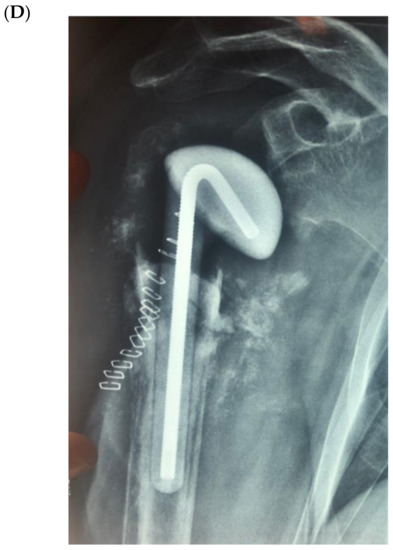

The bone substitute GlassBONE Putty (Noraker, Villeurbanne, France), made of bioactive glass, was routinely employed in revision surgeries requiring bone loss filling in our surgeries. This ceramic is composed of Silicium, Calcium, Sodium and Phosphorous, minerals which are naturally present in the human body; it is in a ready-to-use format and can be injected through the syringe (Figure 1): it may be used both to increase prosthesis-bone interface stability and fill bone defects in PJIS revision surgeries, also contributing to preventing re-infection. In this regard, a peculiar case was reported (Figure 2): infection after percutaneous treatment of a proximal humerus fracture. The pinning removal and the implant of a cement antibiotic spacer were attempted. Finally, an RSA (Equinoxe Shoulder System, Exactech Inc., Bloomington, MN, USA) was implanted with the addiction of bioactive glass to prevent tuberosity defect augmentation and re-infection.

Figure 2.

An infection after percutaneous pinning of a proximal humerus fracture. (A) Preoperative X-ray. (B) The subsequent implanting of a cement antibiotic spacer (red circle underlines bone loss); (C) the final reverse arthroplasty (RSA) with the addition of bioactive glass in the tuberosity defect.